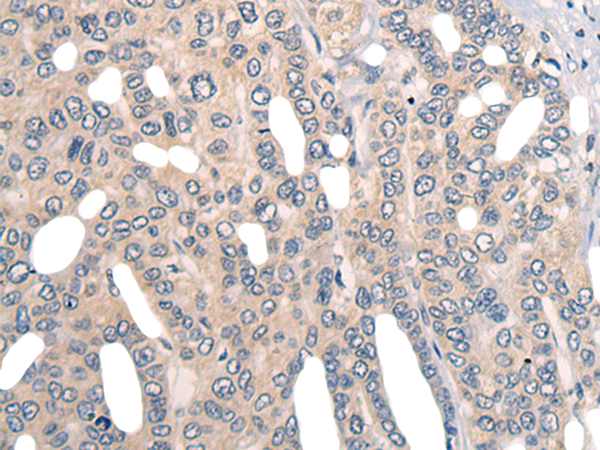

IHC positive control: |

Human lung cancer and Human liver cancer |

IHC Recommend dilution: |

20-100 |